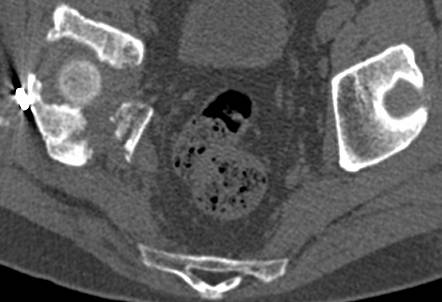

[Ortho] перелом правой половины таза

высылаю дополнительно  сканы.